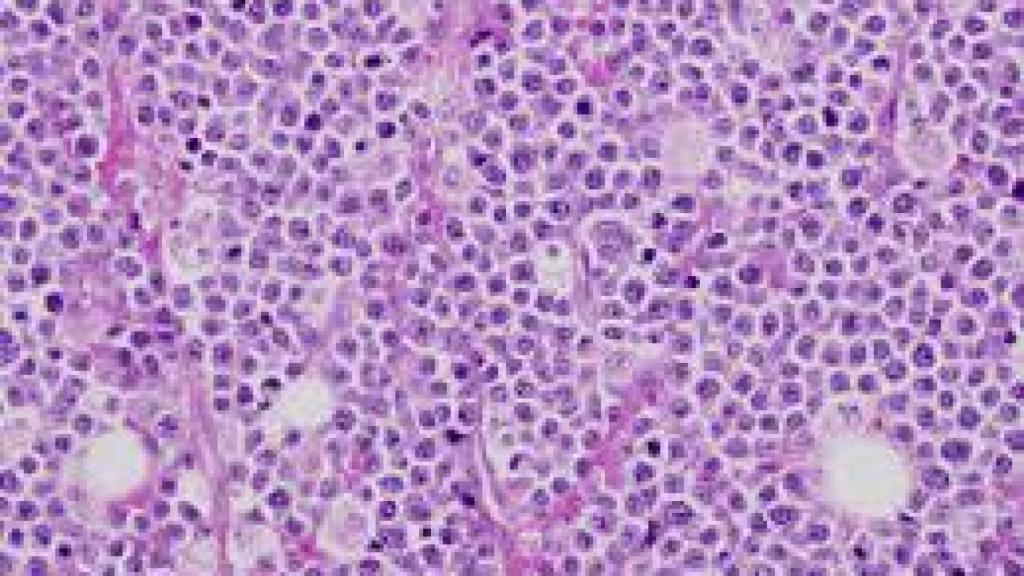

Un mieloma al microscopio. Wikipedia.